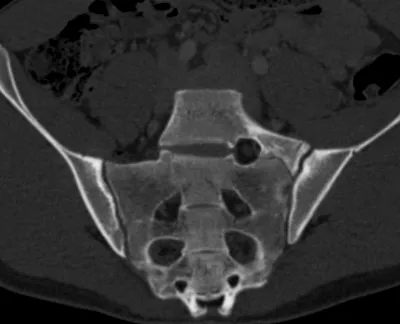

Ischiofemoral space injection for ischiofemoral impingement

CTPelvisAxial+2

4/23/2026